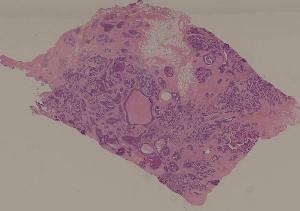

低倍视野

76. Acute pyelonephritis

77. Chronic pyelonephritis

41. Opportunistic infection in the lung

71. Acute transplant rejection of kidney

72. Lupus nephritis

36. Lymphoma

80. Invasive ductal cancer of the breast